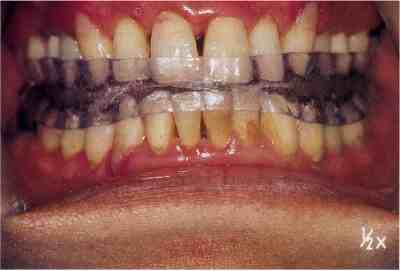

Sleep splint(口腔内装具)を装着した状態

装具装着前

装具装着後

下顎が前方に移動しています。